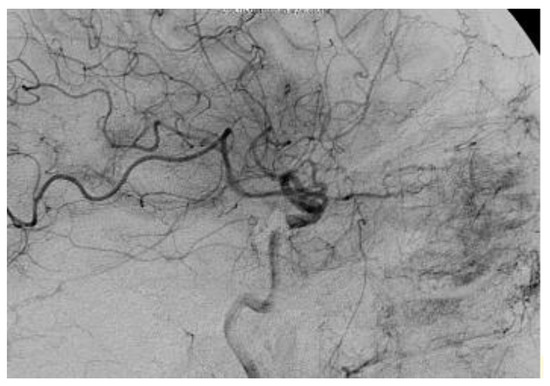

The multidisciplinary team involved in this case comprised neurosurgeons and interventional neuroradiologists. The treatment decided was carried out two times; the first provided the insertion of a cannula needle in the right orbital vein by a trans-palpebral anterior approach, while the second provided for the embolization of the cavernous sinus seat of the venous part of the fistula, through the placement of 5 spirals (Vortex 2x5, Boston), up to the complete exclusion of the fistula. The angiographic control performed immediately after the affixing of the spirals showed the complete normalization of the circulation between the internal and external carotid (Figure 6).

On the third post-operative day, the clinical condition was significantly improved in the following ways: a clear reduction of the exophthalmos and the congestion of the episcleral vessels (Figure 7), a complete recovery of ocular motility (Figure 8), visual acuity improved to 10/10, IOP was 14 mmHg, the disappearance of cotton exudates, and a normalization of the A/V ratio. Fifteen days after the surgery, the ocular conditions were stable.

Figure 6. The selective cerebral angiography revealing a dural fistula of the right cavernous sinus.